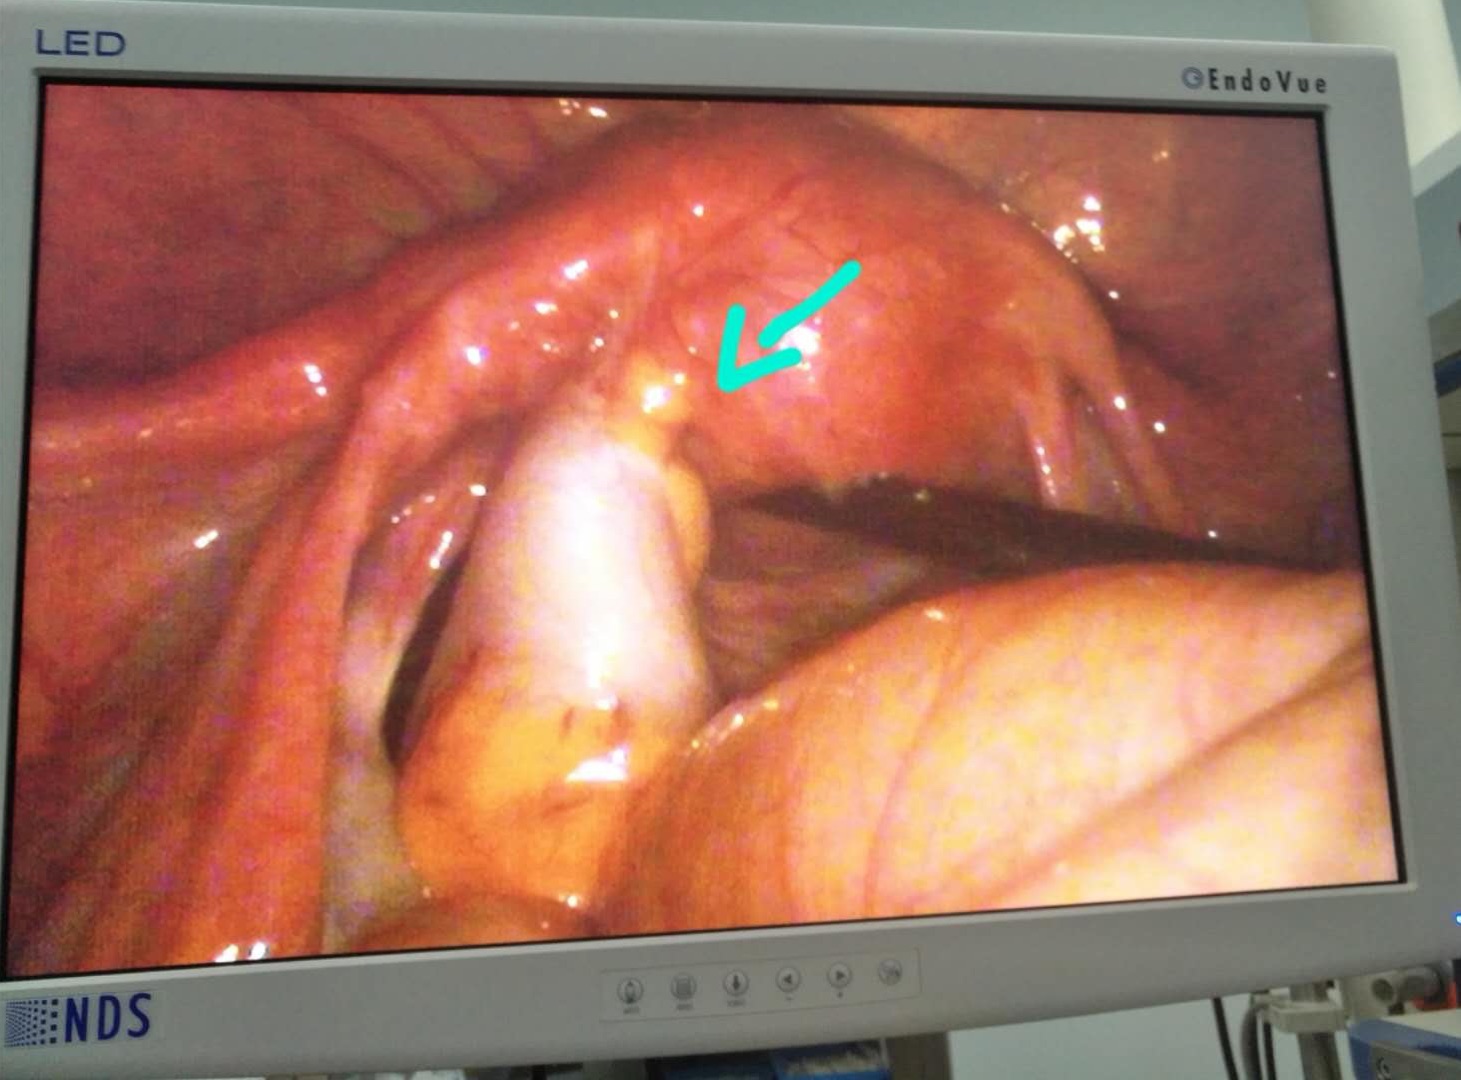

这里附上当时拍的片子,可以看到节育器的一端侵入了子宫肌层壁到了腹腔。而且还发生了肠管粘连,造成小肠浆层损伤!

上图就是一种支架节育环。这种环在一些大幅度的运动时,环的两端难免会与子宫壁发生碰撞,而子宫是非常脆弱的,可以看到节育环的一端已经穿破子宫肌壁出来了。